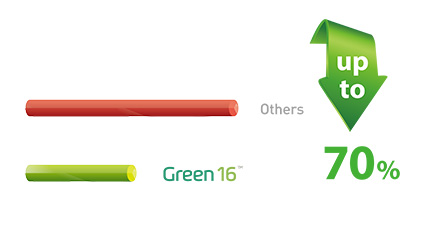

vatech的发展打破了口腔放射摄影的许多惯例。人们一直认为,低辐射的图像质量较差,在临床诊断中毫无用处。然而Green16打破了原有的放射技术,将原有X射线的辐射剂量下降到70%,还能获得高品质影像。